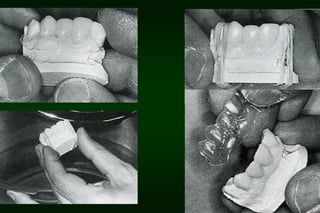

Types of Provisional Restoration II.Customized resin restorations 1. Direct technique a. Direct matrix-assisted • • Elastomeric or alginate impression Vacuum formed plastic template

Types of Provisional Restoration II.Customized resin restorations 2. Indirect technique • • Initial and final polymerizations occur extraorally The first step is preparing a index (e.g. vacuum shell) on study cast prior to tooth preparation visit

Types of Provisional Restoration II.Customized resin restorations 3. Indirect-direct (combination) technique 1. 2. Indirect: polymerization of acrylic resin on mock preparation of teeth Direct: reline is performed intraorally